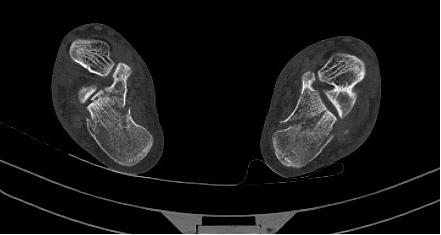

图4术后双跟骨X线